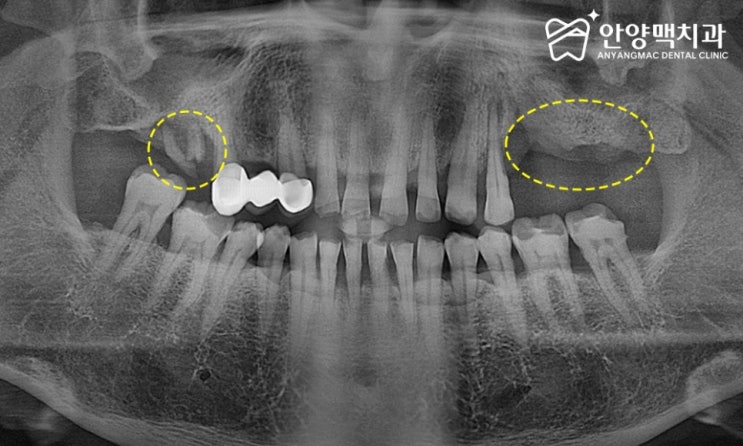

안양매복사랑니발치 세밀하게 위치를 파악한 후

안양매복사랑니 세밀하게 위치를 파악한 후 사랑니는 입안 가장 뒤쪽에 위치한 세 번째 어금니로, 성.인이 ...